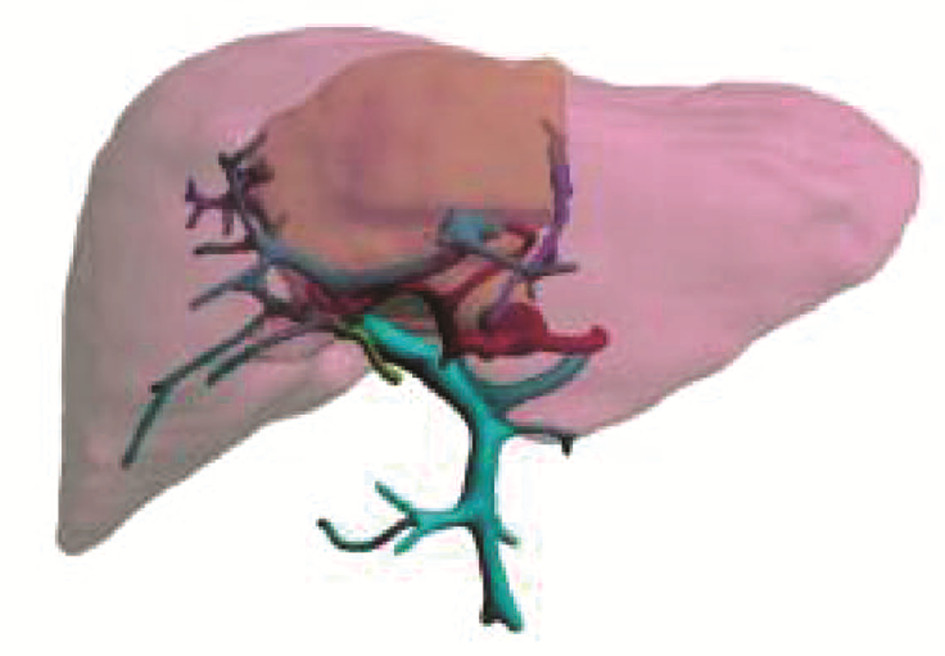

先天性左肝缺如合并肝细胞癌1例报告

王海林, 李敬东, 武国

2023, 39(6): 1408-1410. DOI: 10.3969/j.issn.1001-5256.2023.06.023

摘要(836) HTML (197) PDF (2003KB)(59)

摘要: